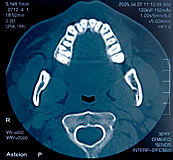

3-D-Aufnahme eines Gebisses